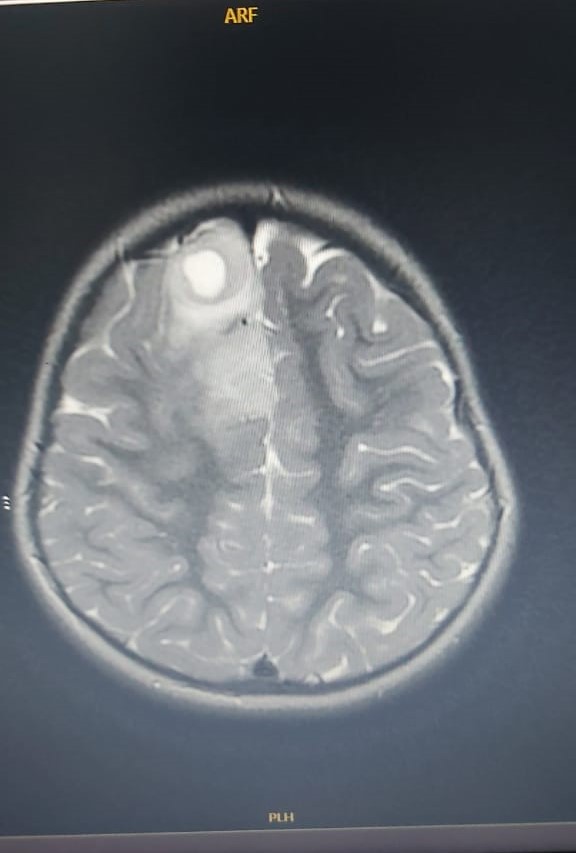

وأوضحت التقارير الطبية الخاصة بـ الطفلة ليان أحمد عماد الطائي بـ الفحوصات الأولية والتصوير بالرنين المغناطيسي للدماغ أنها تعاني من وجود كتلة في الدماغ يُشتبه في أنها ورم دبقي عالي الدرجة، وتلقت علاجًا بـ المضادات الحيوية ومضادات الفيروسات بعد استبعاد التهاب السحايا والتهاب الدماغ، لكن لم يكن هناك أي تاريخ لنوبات أو حالات عصبية سابقة في سجلاتها.

وحسب ما نُشر في التقرير الطبي، أظهرت الأشعات بالرنين المغناطيسي للدماغ وجود كتلة داخل قشرية في الفص الجبهي الأيمن بحجم 3×2×1.7 سم، تحتوي على مكونات نخرية، وتظهر إشارات منخفضة على T1WI وإشارات عالية على T2WI، إذ إن هناك وذمة محيطة تسبب تأثيرًا ضاغطًا مع إزاحة الهياكل الدماغية.